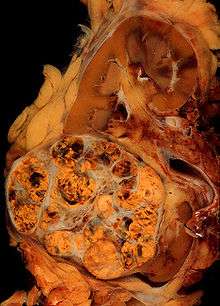

Histopathology

The gross and microscopic appearance of renal cell carcinomas is highly variable. The renal cell carcinoma may present reddened areas where blood vessels have bled, and cysts containing watery fluids.[54] The body of the tumour shows large blood vessels that have walls composed of cancerous cells. Gross examination often shows a yellowish, multilobulated tumor in the renal cortex, which frequently contains zones of necrosis, haemorrhage and scarring. In a microscopic context, there are four major histologic subtypes of renal cell cancer: clear cell (conventional RCC, 75%), papillary (15%), chromophobic (5%), and collecting duct (2%). Sarcomatoid changes (morphology and patterns of IHC that mimic sarcoma, spindle cells) can be observed within any RCC subtype and are associated with more aggressive clinical course and worse prognosis. Under light microscopy, these tumour cells can exhibit papillae, tubules or nests, and are quite large, atypical, and polygonal.

Recent studies have brought attention to the close association of the type of cancerous cells to the aggressiveness of the condition. Some studies suggest that these cancerous cells accumulate glycogen and lipids, their cytoplasm appear "clear", the nuclei remain in the middle of the cells, and the cellular membrane is evident.[55] Some cells may be smaller, with eosinophilic cytoplasm, resembling normal tubular cells. The stroma is reduced, but well vascularised. The tumour compresses the surrounding parenchyma, producing a pseudocapsule.[56]

The most common cell type exhibited by renal cell carcinoma is the clear cell, which is named by the dissolving of the cells' high lipid content in the cytoplasm. The clear cells are thought to be the least likely to spread and usually respond more favourably to treatment. However, most of the tumours contain a mixture of cells. The most aggressive stage of renal cancer is believed to be the one in which the tumour is mixed, containing both clear and granular cells.[57]